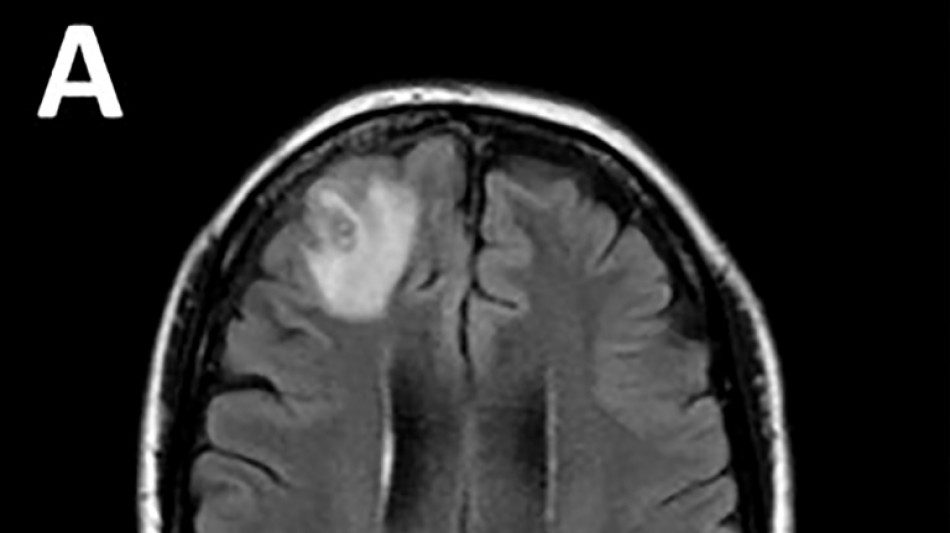

Médicos australianos hallan por primera vez una lombriz parásita en el cerebro de una mujer

Médicos australianos hallan por primera vez una lombriz parásita en el cerebro de una mujer / Foto: © Universidad Nacional Australiana/AFP

Desconcertados, los médicos realizaron una resonancia magnética a una mujer australiana de 64 años después de que comenzara a sufrir lapsos de memoria y notaron una "lesión atípica" en el frente de su cerebro.

Era una lombriz de ocho centímetros llamada Ophidascaris robertsi, que según investigadores son parásitos comunes en canguros y pitones diamantina pero no en humanos.